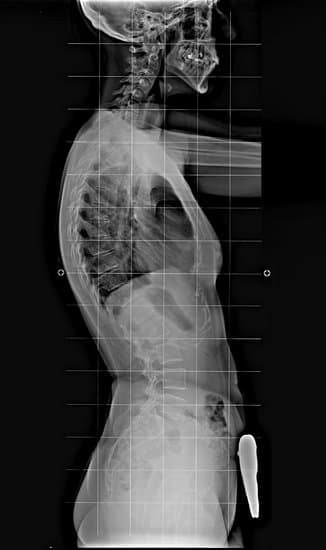

퇴행성 척추 후만증의 진단은 주로 임상적 평가와 이미징 검사를 통해 이루어집니다.

3. 이미징 검사

X-레이: 척추의 구조적 이상을 확인하고 변형의 정도를 평가합니다.

X-레이는 척추의 곡률을 시각화하여 정확한 진단에 도움을 줍니다.